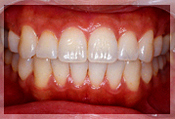

症例6

歯牙のポジションが悪く補綴治療だけでは適切な咬合が行えないケース。矯正治療後審美的にも良好な補綴が行われた。